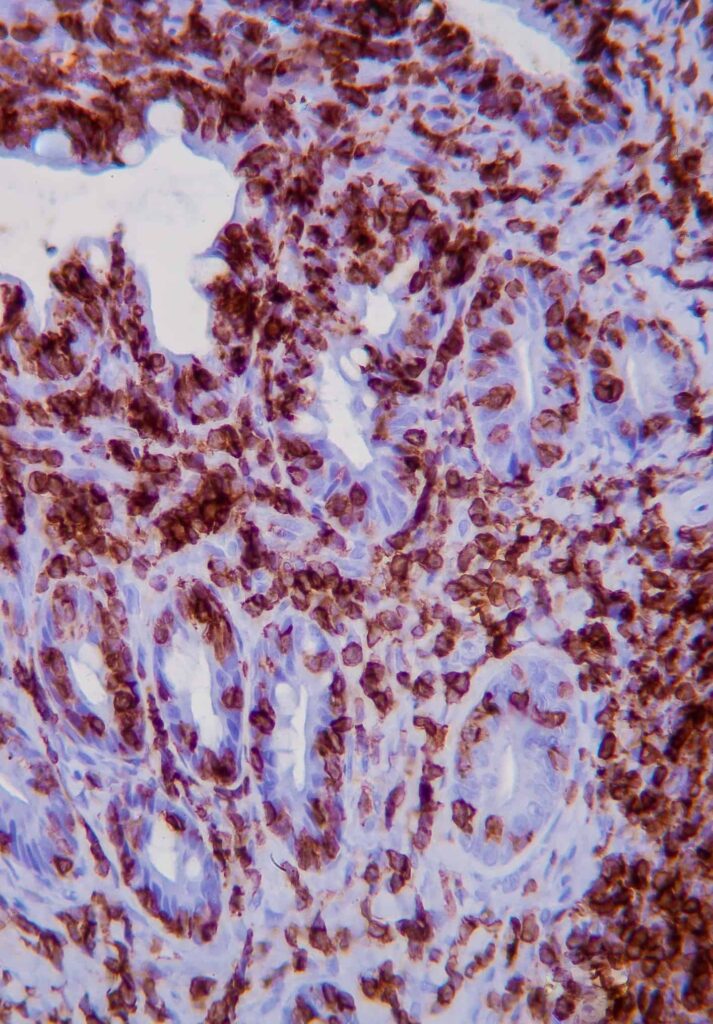

Immunohistochemistry (IHC)[GO(2]

IHC involves the use of antibodies against specific antigens in tissue sections. When lymphoma is suspected, a panel of T and B-cell antibodies (eg, CD3 and CD20) can identify a monomorphic population and establish the cell lineage. Antibodies such as Ki67, pSTAT3 and pSTAT5 have been recently studied and are useful for the diagnosis of LGTIL (Freiche et al, 2021 b).

KEY POINT: The combination of histopathology and IHC is considered the gold standard for diagnosis of LGTIL